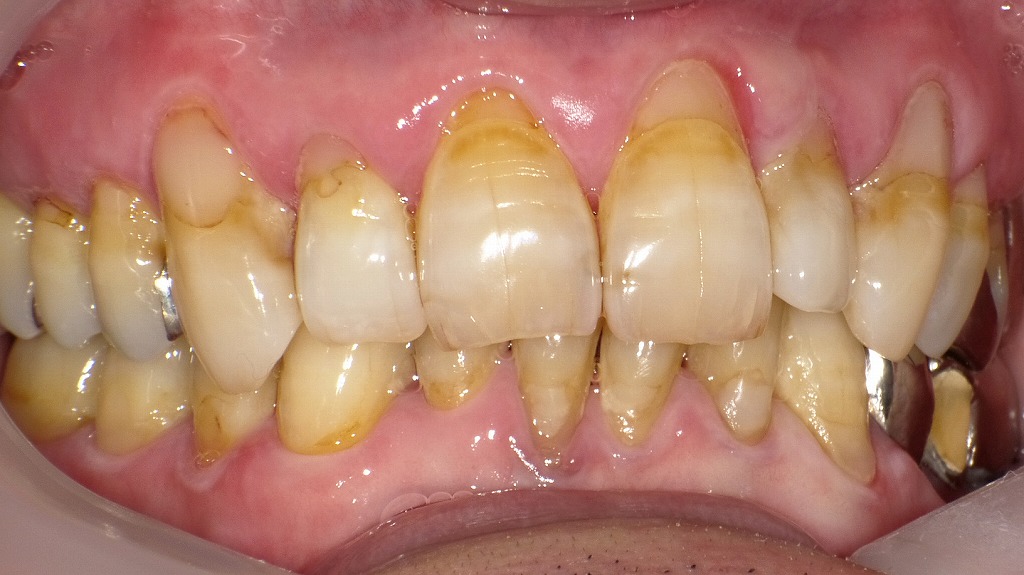

糖尿病と歯周病の悪循環と改善経過|炎症部位・磨き残し・治療効果が一目で分かる症例

糖尿病で歯周病が悪化しやすい理由|腫れ・出血・縁下歯石の典型例

① 正面写真:歯肉の腫れ・出血・プラークの付着が顕著

歯肉が全体に腫れ、軽度の自然出血が確認できる状態。

プラークと縁下歯石が歯周炎を助長し、糖尿病による治癒力低下で炎症が強く出ています。赤矢印で示されるのは、

- 歯肉の腫れ(発赤・膨隆)

- 軽度の自然出血

- 歯肉縁上のプラーク(細菌の塊)と着色

- 歯肉縁下の歯石が疑われる部位

糖尿病があると、血糖コントロール不良により歯肉の炎症が強まり、同じ量のプラークであっても腫れや出血が起きやすいのが特徴です。

また治癒力が下がるため、炎症が長引きやすく、歯周病が進行しやすくなります。② 右側写真:縁下歯石と歯肉の炎症反応の増大